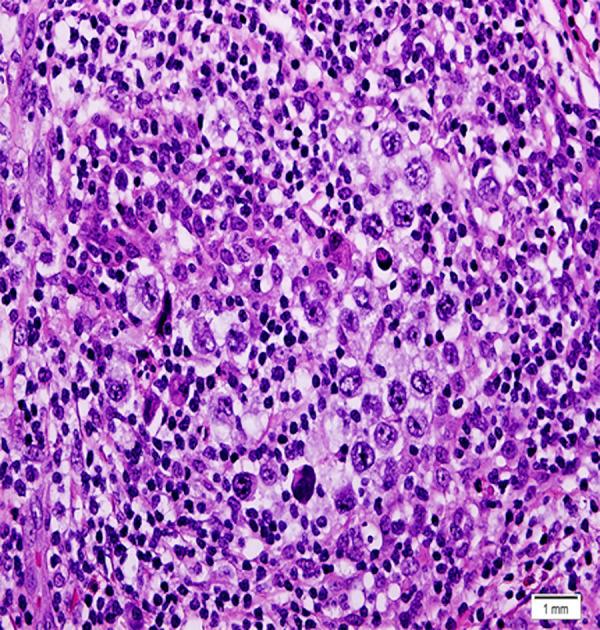

BACKGROUND Myasthenia gravis is a neuromuscular disorder that is strongly associated with thymoma. Although the presence of myasthenia gravis with other tumors is uncommon, approximately 50% of patients with thymoma have myasthenia gravis. Thymic Hodgkin lymphoma should be considered due to the multiple reported cases of patients with myasthenia gravis and Hodgkin lymphoma. In this report, we present the case of 24-year-old woman with myasthenia gravis who was incidentally found to have coexisting thymoma with thymic Hodgkin lymphoma. CASE REPORT A 24-year-old woman with a known case of vitiligo presented with a 2-year history of diplopia and incidental anterior mediastinal mass. Following investigations, myasthenia gravis was diagnosed and managed by pyridostigmine, prednisolone, and azathioprine. Regarding the anterior mediastinal mass, thymoma was suspected based on the presence of myasthenia gravis and radiological findings. She underwent extended transsternal thymectomy. The final histopathological report of the dissected thymus disclosed Hodgkin lymphoma pathology coexisting with thymoma. After the diagnosis of Hodgkin lymphoma nodular sclerosis type IIA was confirmed, 6 cycles of chemotherapy were administered. Four years of follow-up revealed no evidence of Hodgkin lymphoma. However, her symptoms of myasthenia gravis persisted despite Hodgkin lymphoma remission. CONCLUSIONS There is an unclear association between myasthenia gravies and Hodgkin lymphoma. Prior reports revealed regression of myasthenia gravies following Hodgkin lymphoma management, which suggests that myasthenia could be a complication of Hodgkin lymphoma. However, in our case, myasthenia gravis persisted after Hodgkin lymphoma management; therefore, further studies are needed to explore this association.

一名 24 岁女性,患有白癜风,出现复视 2 年,偶然发现前纵隔肿块。经过检查,诊断为重症肌无力,采用吡啶斯的明、泼尼松龙和硫唑嘌呤进行治疗。鉴于前纵隔肿块,考虑到重症肌无力和影像学发现,怀疑为胸腺瘤。她接受了广泛的胸骨切开胸腺切除术。解剖胸腺的最终组织病理学报告显示霍奇金淋巴瘤与胸腺瘤并存。在诊断为霍奇金淋巴瘤结节性硬化型 IIA 后,给予 6 个周期的化疗。4 年的随访未发现霍奇金淋巴瘤的迹象。然而,尽管霍奇金淋巴瘤缓解,她的重症肌无力症状仍持续存在。